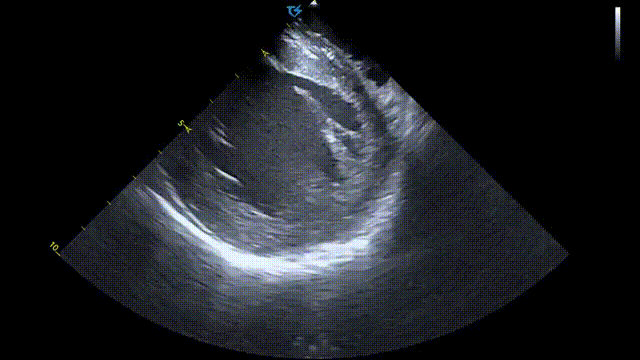

术前ICE左房血栓筛查

术前术后心包对比:

术前心包基线扫描

术后心包检查